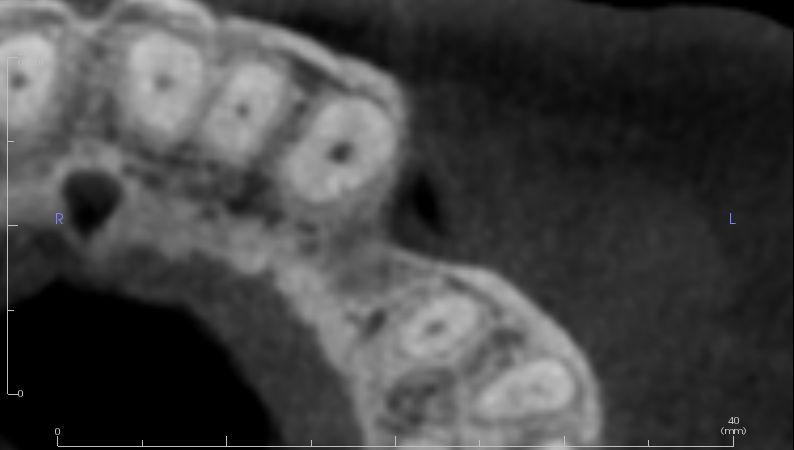

To better understand the patient's overall dental health, a full mouth CBCT scan was taken, confirming the presence of a bony defect in the area where tooth 24 had been surgically extracted.

Intraoral scans were completed using the Trios 4 intraoral scanner and a H8 x D 15cm craniofacial field CBCT was taken.

Pre-surgical planning began with acquiring high-quality diagnostic data, including TRIOS intraoral scans and CBCT imaging. The data was imported into 3Shape Implant Studio, where I designed a virtual crown for tooth 24 and planned the precise positioning of the implant, considering critical factors such as sinus proximity, adjacent roots, bone density, and the location of the bony defect.